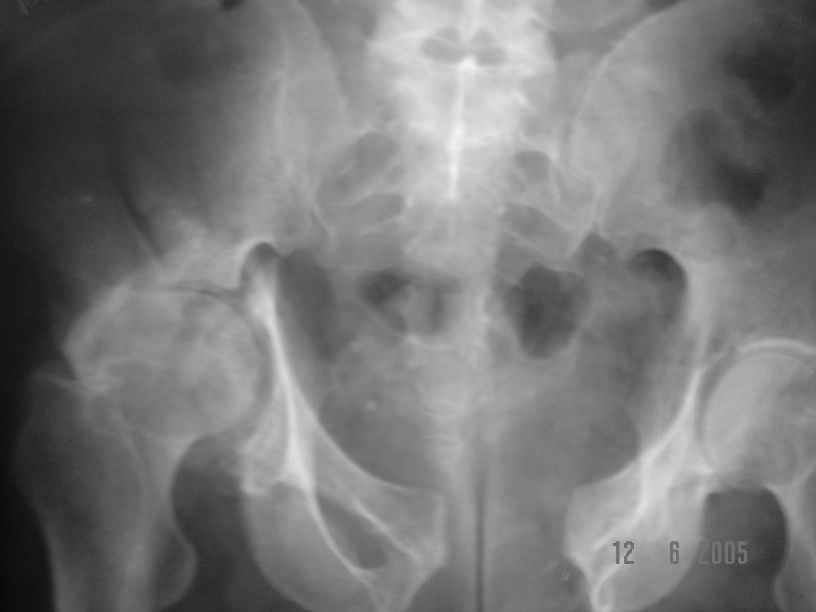

Dear All, The patient came to us for opinion regarding this # of pelvis which he sustained 5 months back.

He gives history of being on skin traction for 3,5months. After that he was advised partial weight bearing to be graduated to full weight bearing. Now the patient has difficulty in weight bearing as it is painful. He can walk a few steps only with the help of a walker. Hip movements are restricted and painful. Fl-90* ER-10* IR-0, shortening-4cm. He also had # of humerus and radius/ulna, which were plated and have united. The serial x-rays of the pelvis/Hip during these 5 months show that the hip joint has been in the same position. I have the CT pictures also but not digitalized as yet.

It is a displaced and ununited fracture of the acetabulum, probably type C (AO). The pelvis is not fractured from what one can see of the sacro iliac joint.

Sorry missed the wide open pubic diastasis.

I think, if symphysis is unstable at first you must open and stabilize symphysis by plate or

external fixator or may be use both together.